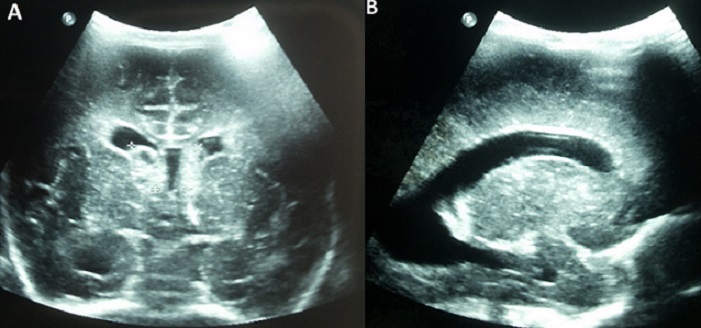

Intraventricular hemorrhage (IVH) occurs rarely in term infant, since subependymal area is a transient structure in fetal life. IVH in term infant indicates generally that it happened prenatally. Congenital cytomegalovirus (CMV) infection is frequent, occurring in 1% of live births. It is a severe infection leading to developmental defects, especially sensorineural deafness. The diagnosis of congenital CMV infection is rarely evoked in term eutrophic newborn. We report a term male neonate born to a 32-year-old mother gravida 2, para 2. Pregnancy was uneventful. Ultrasound follow-up was unmarked. The newborn was eutrophic, birth weight was 3400g, length was 49cm, and head circumference 33cm. Neonatal examination showed no anomalies. On the first day of life, blood cells count performed for suspected materno-fetal infection discovered fortuitous thrombocytopenia at 30 x 109/L. Within the second day of life, platelet level dropped to 20 x 109/L. Management of thrombocytopenia included multiple platelet transfusion. Cranial ultrasound on day one of life showed bilateral subependymal hemorrhage with cysts (A) and hydrocephaly (B), signs of prenatal occurrence. Platelet phenotypage rules out the diagnosis of allo-immune thrombocytopenia. Laboratory testing for rubella was negative. Blood PCR CMV was positive. Liver function tests noted the absence of hepatic cytolysis and cholestasis. The newborn received intravenous Ganciclovir® therapy. Hearing screening before discharge was negative. Bilateral deafness was diagnosed at 3 months of life.